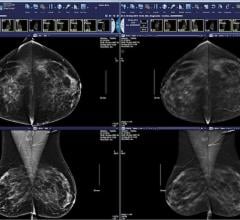

October 14, 2014 — McKesson Radiology Mammography Plus version 2.0 offers users unrestricted access to multimodality breast imaging with all the advantages of a robust picture archiving and communications system (PACS).